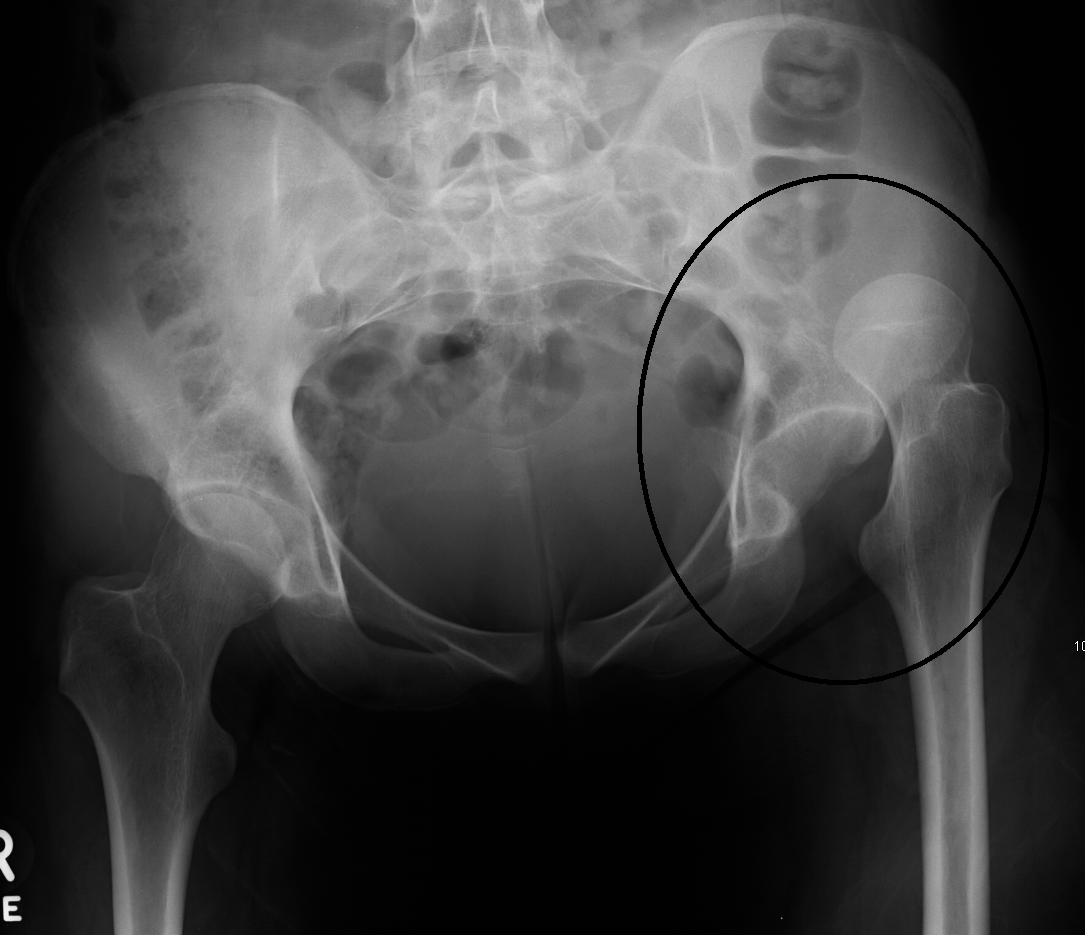

Chụp X quang

- Cần chụp X quang xương chậu và khớp háng ở tư thế thẳng. Nếu ở hõm khớp có một bất thường nhỏ chụp tia chếch 450 ra sau vào trong để phát hiện mảnh vỡ phía sau hõm khớp.